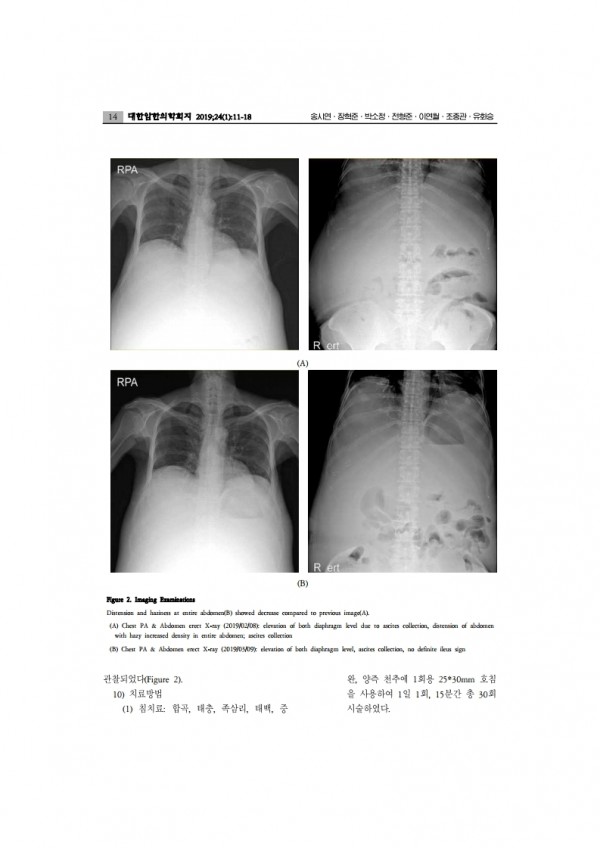

전이성 평활근육종 환자의 통합 암 치료에 대한 증례보고